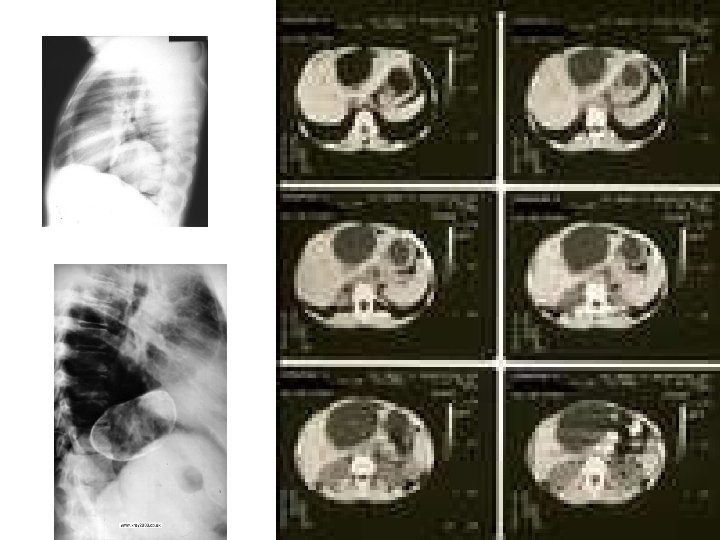

Hydatid cyst

Hydatid cysts